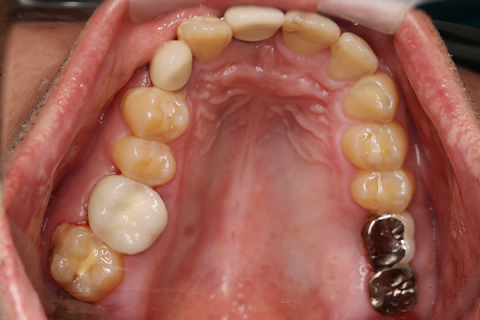

症例4

- 年齢・性別

- 60歳

- 治療期間

- 6ヶ月

- 抜歯

- 残根抜歯のみ

- 治療費

- 198万円

- 備考

- 右上5.6 右下5 左下4.5.6欠損

- 治療内容

- 6本のインプラントを右左側に2回に分けて埋入

- 施術の副作用(リスク)

- オペによる知覚障害。インプラントによる歯肉炎。インプラント脱落。